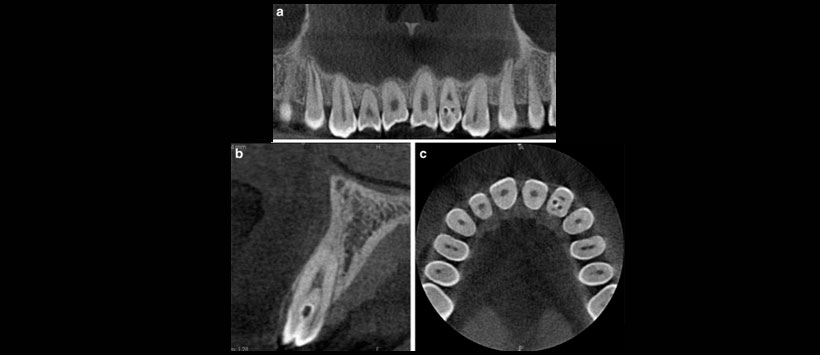

Los dientes invaginados (DI) puede reconocerse en casi todos los tipos de radiografías dentales, pero la ventaja del examen de tomografía computarizada con haz cónico (Figura 1 y Figura 2) es la evaluación del tipo de malformación. La siguiente clasificación ampliamente aceptada de DI fue propuesta por Oehlers :

Figura 2: a) Ejemplo de aparición bilateral de 2 dientes supernumerarios invaginados, incorrectamente desarrollados y situados en zona de la 11 y 21 en  una vista panorámica, b) Imagen de sección transversal,  c) plano axial